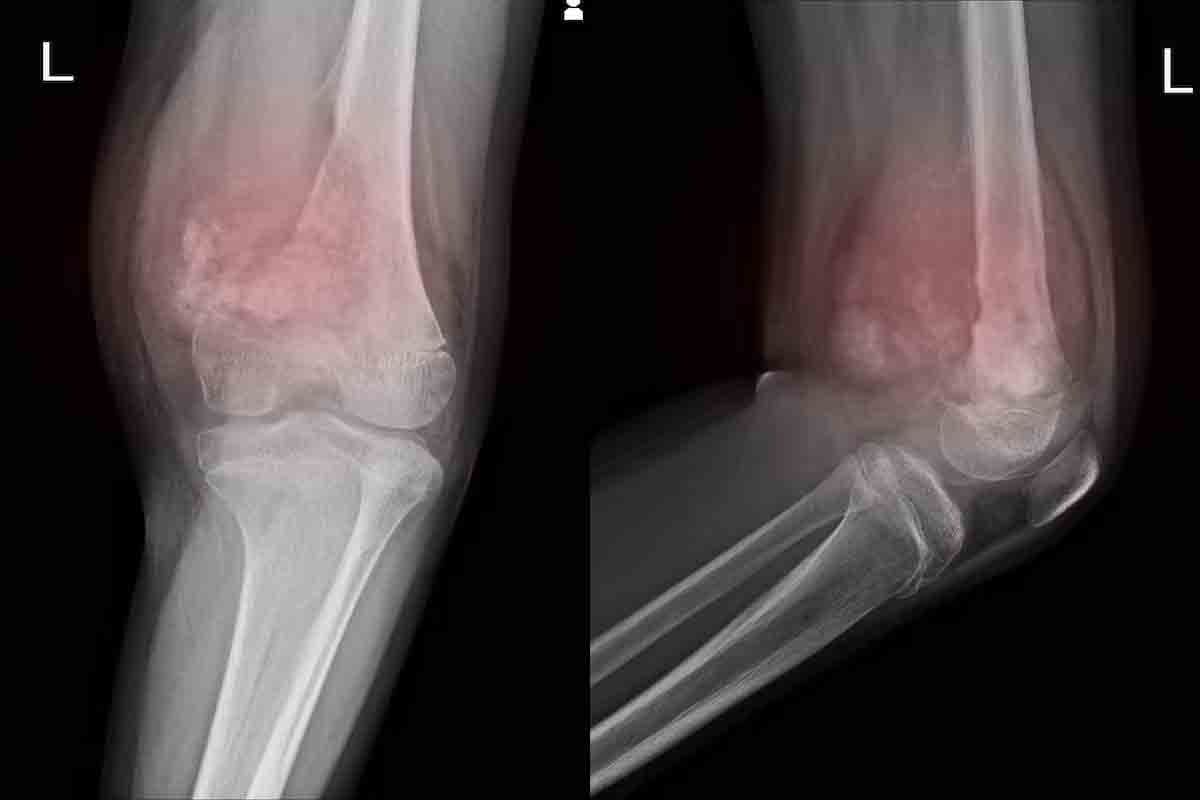

Colorectal, Prostate, and Skin Cancers: Prevalence and Risk

Colorectal, prostate, and skin cancers are also common worldwide. Colorectal cancer is a big problem, mainly in older adults. Prostate cancer is a top cancer for men, with different rates in different places.

Skin cancer, including melanoma and non-melanoma, is a big concern. This is true for people who spend a lot of time in the sun.

Each of these cancers has its own risk factors and patterns. For example, colorectal cancer is linked to diet, exercise, and genes. Prostate cancer is influenced by age, family history, and ethnicity. Knowing these helps us create better prevention and screening plans.